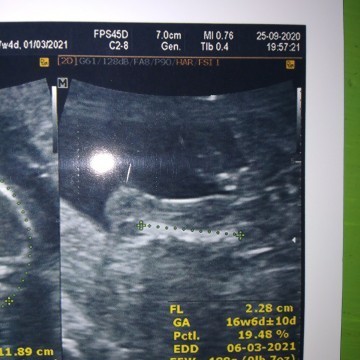

มาอวดภาพอัลตร้าซาวด์กันหน่อยแม่จ๋า 🤰🏻👼🏻 ชาย หรือ หญิง กันนะ?

โพสใต้คอมเมนต์กันได้เลยนะแม่ ♥️ แอดอยากเห็นๆ 7/11/2563